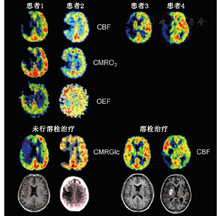

脑卒中早期,PET研究[40,41,42,43]发现脑缺血区域由不同的组织构成。测量时(通常在脑卒中发生后的几个小时)rCBF低于12 ml·100 g-1·min-1的组织或CMRO2低于65 mmol·100 g-1·min-1的局部区域在后期CT扫描中被发现是梗死区域。缺血区域残存的CMRO2是神经元相对完整的一个指标,预示该区域CBF将减少至12~22 ml·100 g-1·min-1。这种不完全的缺血灌注模式[41]是一个缺血半暗带,该区域的OEF增加(由正常值40%上升到80%)。PET研究将缺血区域分为3个部分:缺血核心区(12 ml·100 g-1·min-1),通常呈现出坏死;缺血半暗带区(12~22 ml·100 g-1·min-1),是仍然存活的组织,但可能发生梗死,也可能恢复功能;低灌注区(22 ml·100 g-1·min-1),没有受到血液供应不足的明显损害(图2)。缺血半暗带的进展及转化为梗死是一个动态过程,不可逆损伤的发生也是从缺血中心向周边进展。PET可对这个病理进展过程进行跟踪,并对动物模型和急性脑卒中患者的生理变量进行研究[44,45,46](图2)。

急性缺血性脑卒中的疗效监测也是建立在显像研究的基础上,缺血半暗带再灌注后可改善神经功能的损害(图5):患者接受rtPA治疗后的再灌注量与对照组相比显著增加[64]。在脑卒中发病后的3 h内,H215O PET CBF显像能够确定再灌注可修复组织的容积,并与梗死3周后MRI的梗死容积对比[65]。最初缺血的区域(即血流量低于阈值12 ml·100 g-1·min-1)再灌注后血灌注量接近正常水平,并预测在3周内临床症状得到明显改善。在一个12例的小样本研究中,灌注量低于脑卒中临界值的灰质,仅22.7%在溶栓治疗后会发生坏死,这意味着有很大一部分缺血组织再灌注治疗后仍可修复。另一个11例患者的PET研究[66]发现,只有当11C-氟马西尼在皮质摄取不减少或不低于白质平均摄取值的3.4倍时,缺血组织的再灌注才有效。这种神经元完整性的标志物可作为不适宜接受治疗的不可逆损伤组织的一个指标。

缺血性脑卒中病灶的早期PET研究[30]发现,其代谢和血流量减少的范围超过其受损组织形态学改变的范围,这与SPECT显像发现类似。最显著的表现是病灶对侧小脑的脑血流减少和代谢减低,称为交叉性小脑失联络[84],在脑卒中患者立即出现,在涉及小脑-皮质-脑桥途径而又成功地再灌注治疗的可逆性病变中持续存在(图5)[85]。交叉性小脑失联络是由一些神经元介导的效应,且因急性缺血而失活的部位已被证明位于小脑[86]。另外,在同侧皮质和基底神经节也存在脑血流的减少和代谢减低,但由于选择性的神经元缺失或血液供应不足也会影响到这些区域,故具体原因不明。然而,在非缺血性病变(如脑肿瘤和颅内血肿)中也会出现这种效应,因此相对于原发灶性质为何,其似乎与病变发生部位关系更为密切[84]。在皮质和皮质下病变中,顶叶和额叶梗死通常引起同侧基底节和对侧小脑的脑血流减少和代谢减低。该效应可通过皮质-脑桥-小脑途径损伤来解释。基底神经节的梗死可引起同侧大脑及对侧小脑失活。丘脑梗死主要影响病侧皮质,只有病变累及内囊时才会出现明显的小脑失活[87]。脑干和小脑梗死通常不引起前脑结构的不对称失活。交叉失联络不能通过常规的PWI参数检测到。临床症状可通过病灶远处的改变来解释,交叉失联络的程度与临床功能的缺损程度(脑卒中评分量表评估)与之后的功能恢复程度相关[88]。脑功能网络特定区域的失活和再激活在临床症状的出现和恢复中发挥着重要作用。